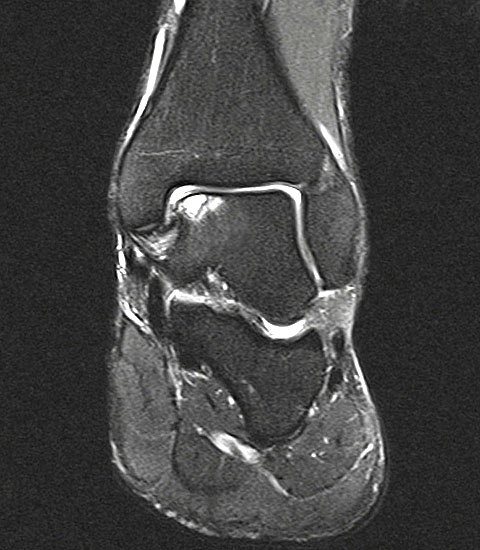

Abbildung 1: Osteochondrale Läsion der medialen Talusschulter mit subchondralem Begleitödem und Zyste.

Abbildung 1

• MRT des Sprunggelenks zur Beurteilung der Knorpelläsion, möglichen subchondralen Zysten, nekrotischen Knochenarealen und anderen Begleitpathologien (Abbildung 1).

Die Darstellung der weiteren Operationstechnik erfolgt am Beispiel eines medialen Zugangs bei einer Osteochondrosis dissceans mit subchondraler Zyte der medialen Talusschulter (siehe MRT Abbildung 1).